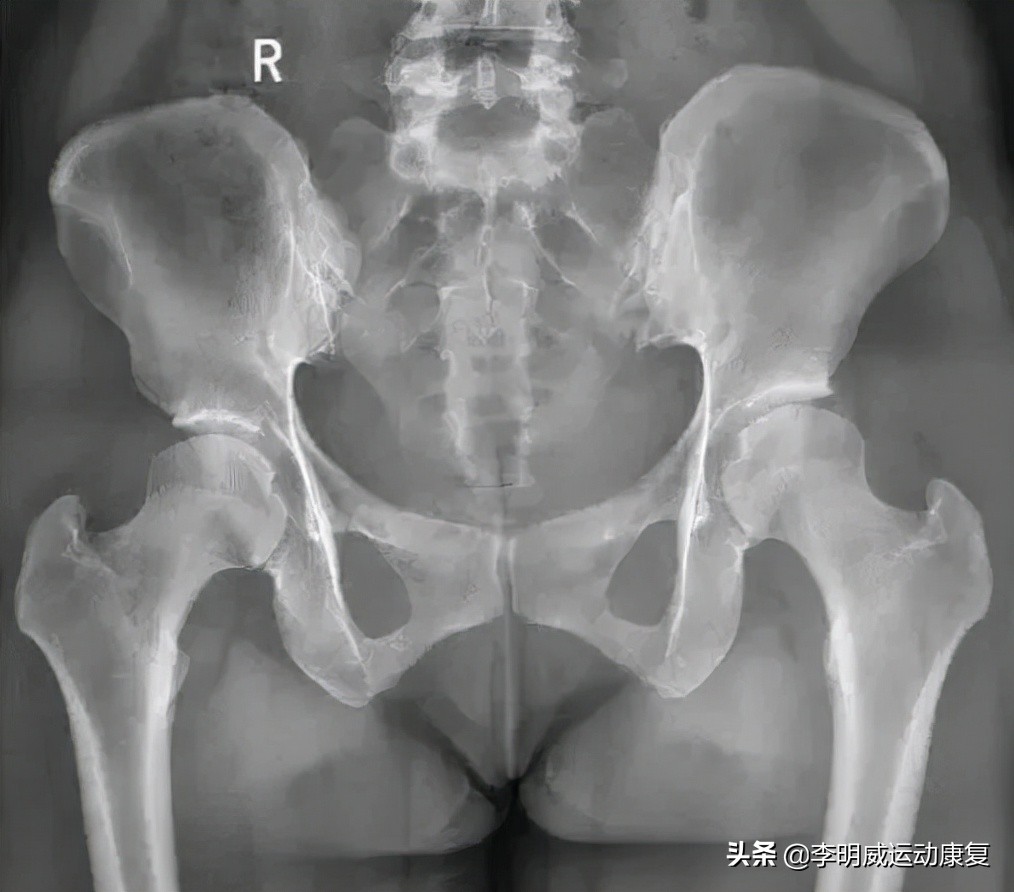

首先,骨盆在解剖学上分成了四块大骨头,分别为左右两个髋骨(由髂骨,坐骨,耻骨密合而成),骶骨,和尾骨。

其次,骨盆在运动学上来说又加上了第五节腰椎和骨盆之间的腰骶关节,以及骨盆和股骨之间的髋关节。而髋关节也是人身上活动范围最大的关节之一。

另外,骨盆内部的骶髂关节错位和紊乱、耻骨联合错位、髋关节活动度降低等,也会导致腰臀腿痛。